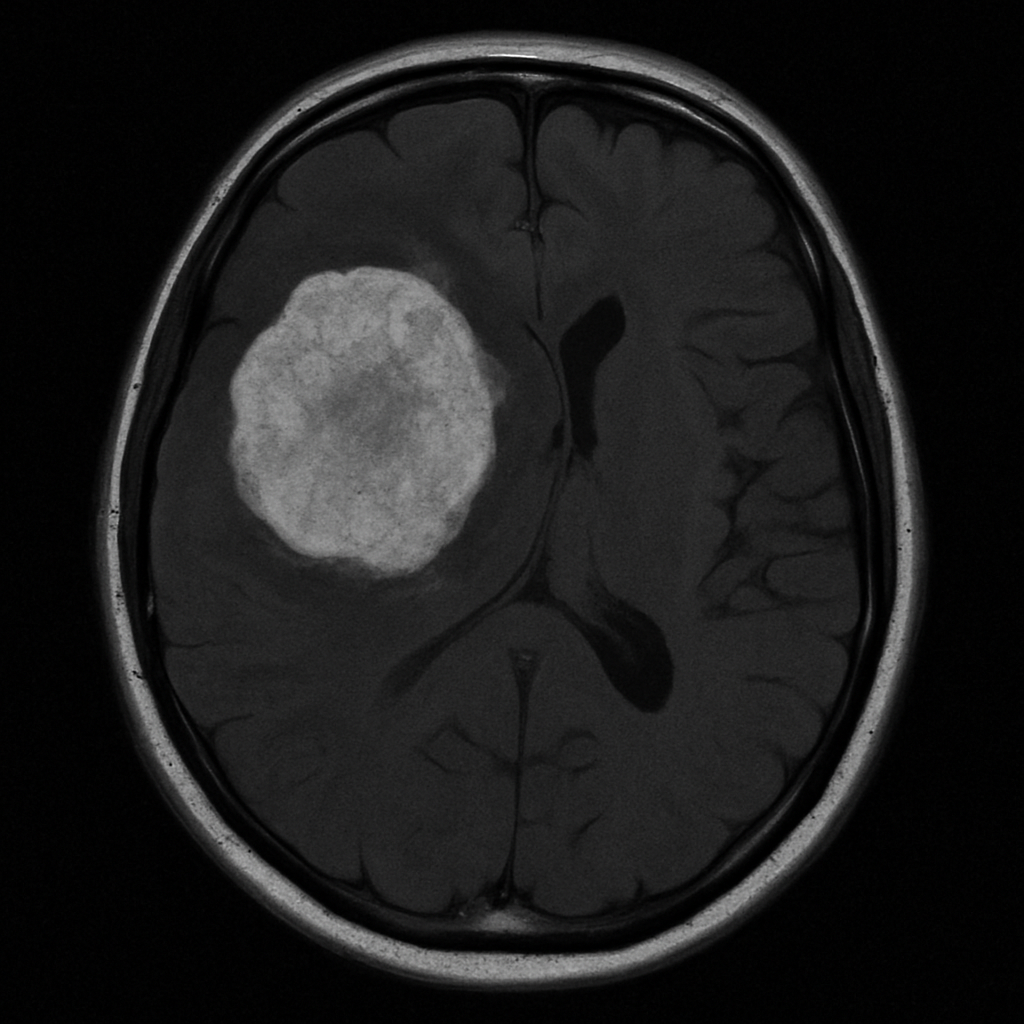

Imaging Studies

MRI and CT scans are critical in providing detailed images of the brain, helping to identify the presence, size, and location of a tumour. Advanced imaging techniques, such as functional MRI or PET scans, can offer additional insights into tumour activity and brain function.